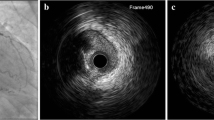

High-definition (HD) IVUS imaging catheters use 60-MHz frequency compared to 40 MHz of standard IVUS. These catheters offer a better resolution, higher pull-back speeds up to 10 mm/s, and higher frame rates of 60 frames/s. The higher resolution allows the evaluation of fibrous and lipidic plaque, tissue prolapse, and improved visualization of stent struts to identify malapposition, while maintaining the known advantages of IVUS of greater depth penetration compared to OCT [23] (Fig. 2). HD-IVUS has been shown to better visualize struts of bioresorbable scaffolds compared to standard IVUS [24]. Stent thrombotic material, stent malapposition, and fibrous cap and calcium thickness are still better evaluated with OCT [25].

High-definition (HD) intravascular ultrasound (IVUS, top row) compared to optical coherence tomography (OCT, bottom row). A) The intima, media, and adventitia are clearly visualized with both HD-IVUS and OCT. B) Fibrous plaque. C) Lipidic plaque. D) Tissue prolapse and subtle stent malapposition are visible after stent implantation, particularly with OCT. E) Calcium underlying stent struts. F) A distal edge dissection is seen clearly visualized by OCT but on IVUS only appears as discontinuation of the intimal layer without a visible flap or hematoma. Reprinted from Chin et al.23 with permission from Elsevier